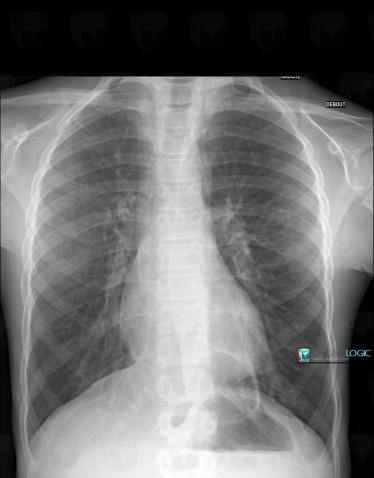

Hiatal hernia, Diaphragm, X rays

Here is the specific information in the key image above:

- Diagnosis Hiatal hernia (link to Diaphragmatic hernia), Location(s) Diaphragm, with gamuts Unilateral elevated diaphragm